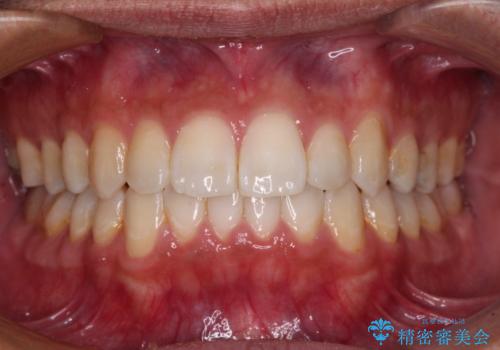

- 前歯のデコボコを気にして来院された患者様です。

上顎右側犬歯が八重歯になっており、それによって奥歯が前方に移動しているため、右側の咬み合わせの改善が必要と判断されました。

マウスピース矯正では改善に時間がかかる、あるいは改善しきれない可能性があることを伝えたところ、短期間で確実に治療ができるワイヤー矯正を選択されました。

より治療を速やかに行うため、上顎右側にアンカースクリューを使用し、目標としていた1年半ほどで治療を終えることができました。